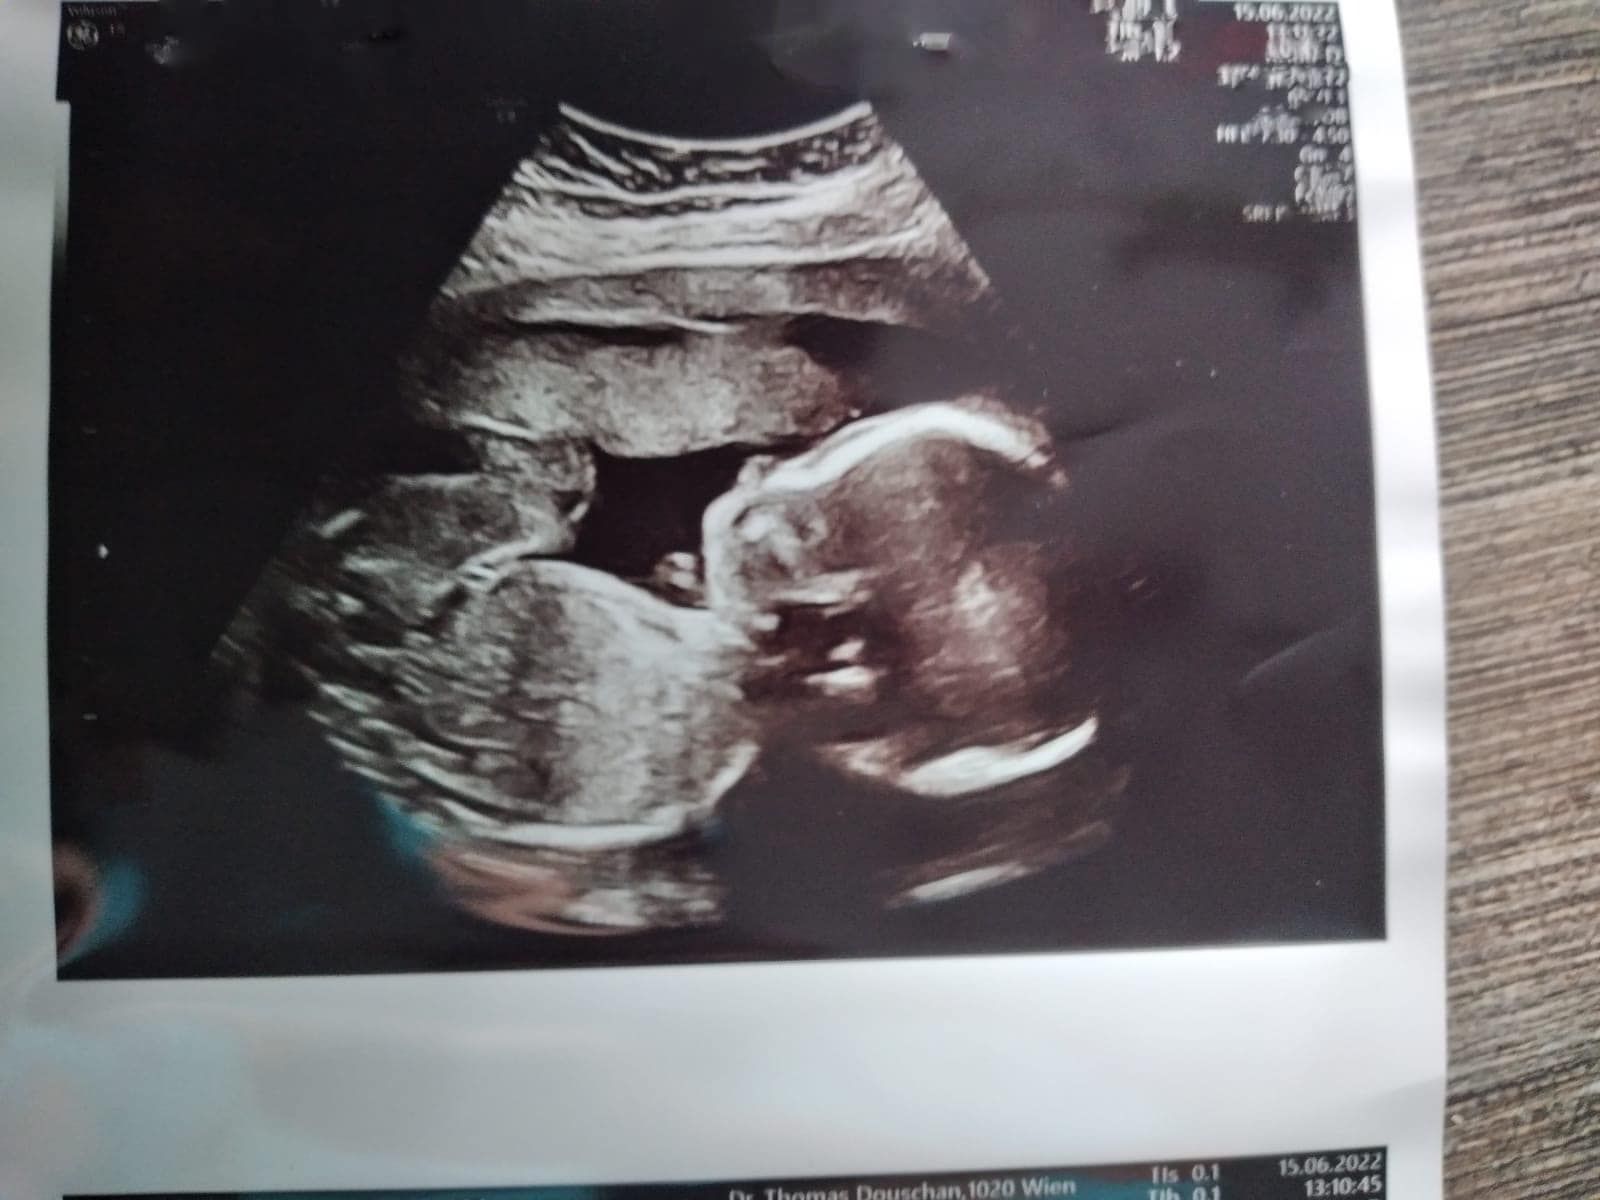

Sie waren seit 16 Jahren ein Liebespaar. Schon lange hatten sich Caroline F. und Thomas O. (Namen geändert) aus dem Bezirk Korneuburg (NÖ) auch ein gemeinsames Kind gewünscht. Doch weil beide Niederösterreicher Vorerkrankungen hatten, schien ihnen dieses Glück bis zuletzt verwehrt. Anfang des Jahres kam dann die freudige und völlig überraschende Nachricht: die 38-Jährige war schwanger. Im Oktober soll ihr Wunschbaby Paul (Name geändert) zur Welt kommen.